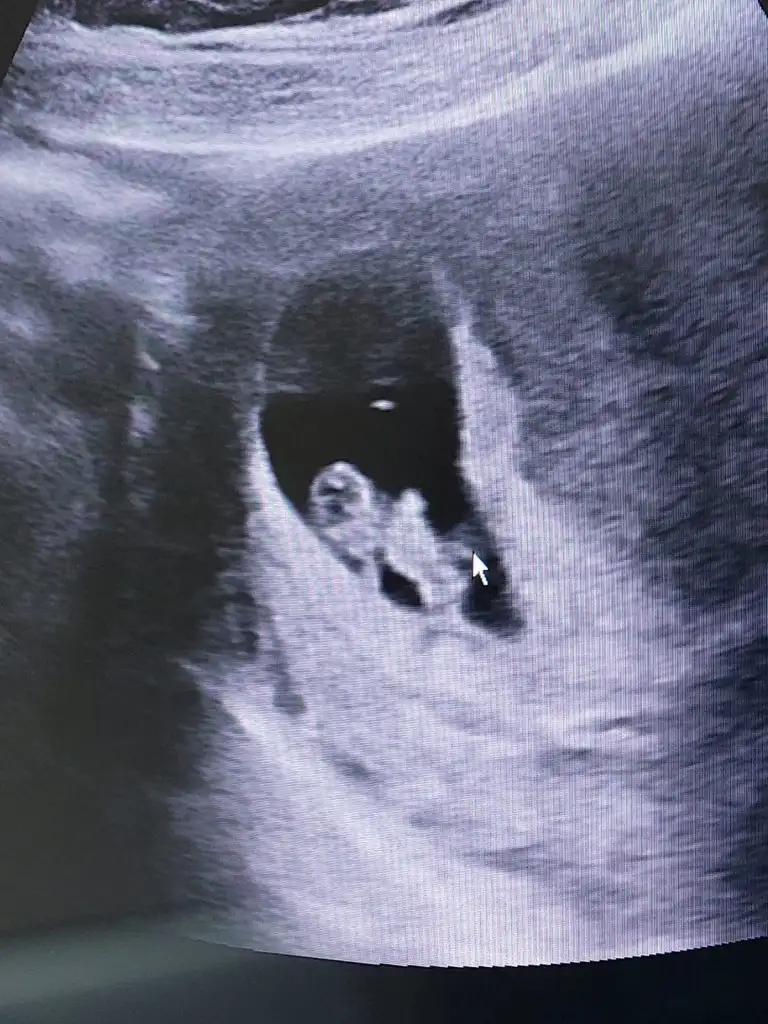

Teşekkür ederim hayırlısı inşallahtahmin için biraz büyükama iki ve üçüncü foto çok net kız canım

mutlaka haberlerinizi bekliyorumTeşekkür ederim hayırlısı inşallahhaftaya kontrol var öğrenince yazarım size de